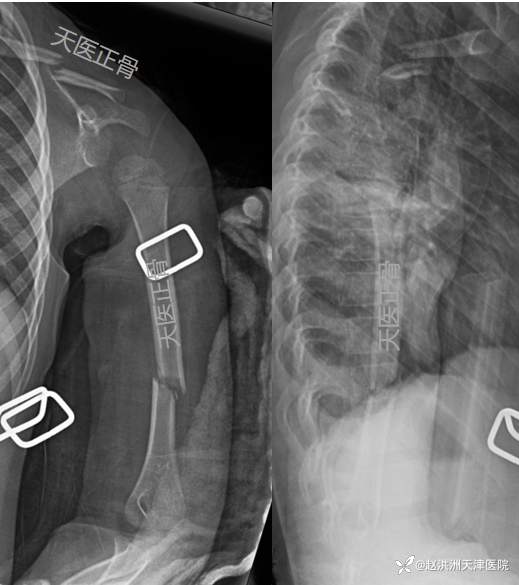

6周临床愈合良好,去除固定,肩肘关节功能锻炼

8周影像:锁骨、肱骨骨痂开始塑型

12周力线矫正良好